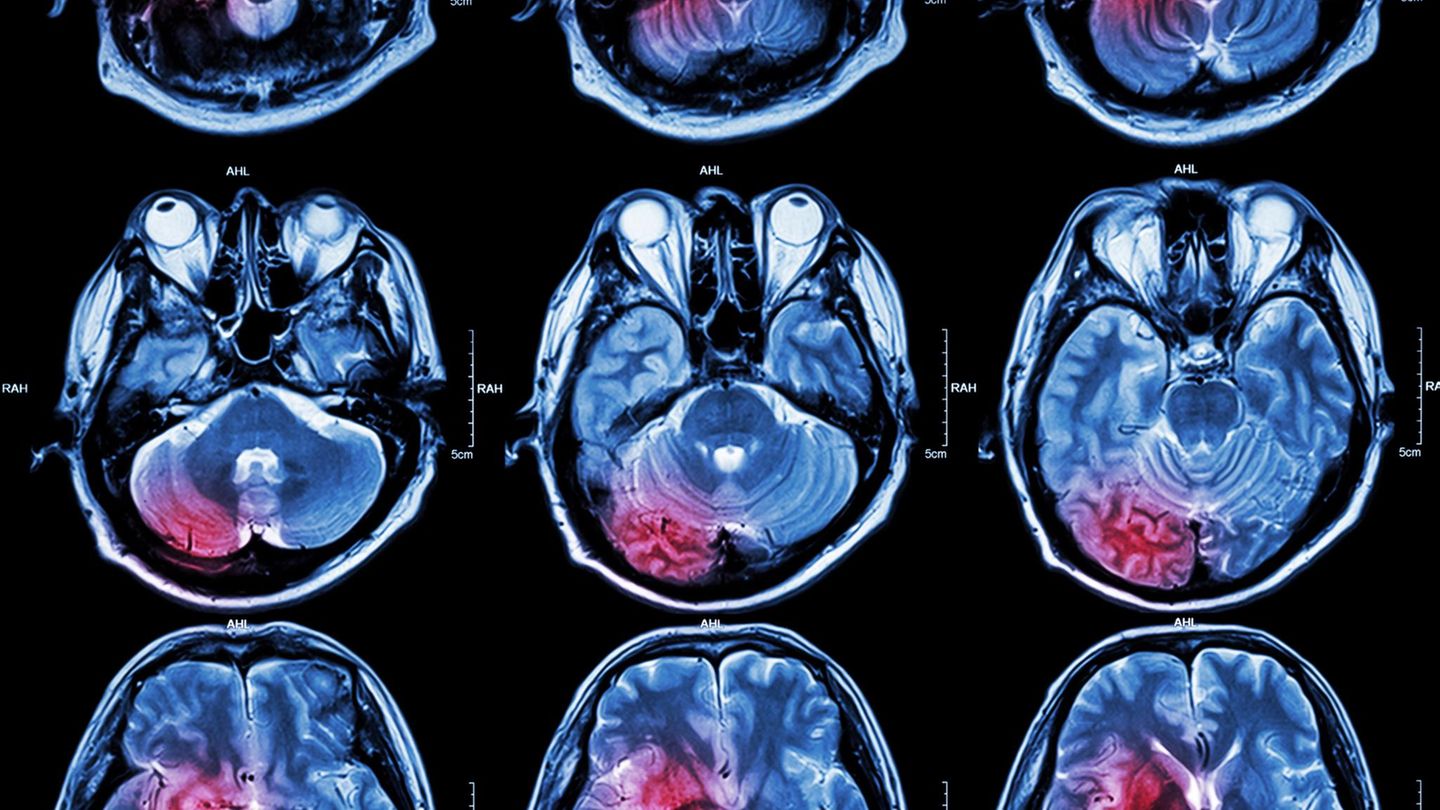

MRT Aufnahmen eins Kopfes mit Hrintumor

Melanom im Gehirn – Krebs am falschen Ort

Das primäre leptomeningeale Melanom entsteht direkt in den Hirn- oder Rückenmarkshäuten. Kopfschmerzen, Krampfanfälle oder neurologische Ausfälle sind häufige Symptome. Seine extreme Seltenheit liegt im Ort seines Ursprungs: Im zentralen Nervensystem existieren nur wenige Melanozyten. Je geringer die Zahl potenzieller Ursprungszellen, desto geringer das Krebsrisiko – ein einfaches, aber entscheidendes biologisches Prinzip.